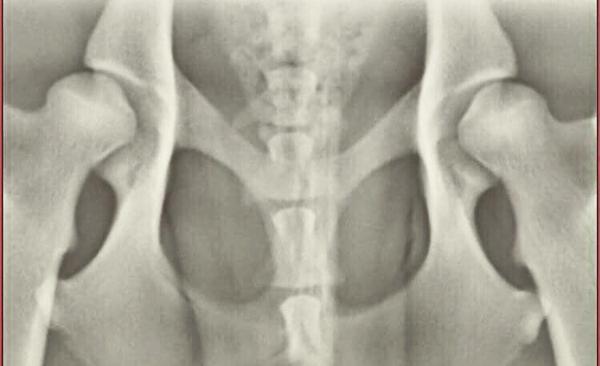

Jeg ville høre om i hundekyndige ville tage et kik på mine hoftebilleder (af hundene selvfølgelig!)

Hvad er et bud på en hoftestatus på dem? Den ene er en tæve og den anden en han, men det kunne i vel allerede se

Udover det, så ved jeg ikke hvad man har gjort med benene på det nederste. Det er forhåbentlig ikke officielle HD billeder?

Jeg formoder at den sidste er hannen (der er ihvertfald en umiskendelig skygge

Billedet er ubrugeligt, desværre, der skal et nyt til.

Hvis man ignorerer den forkerte benstilling, så er den øverste hårdest ramt.

Den nederste har noget bedre kontakt og langt bedre vinkler uden jeg dog synes de ser godt ud. Knoglerne ser ikke pæne og harmoniske ud, men hvor meget den slags vægter tør jeg ikke sige. Hvis man kun kigger på hvor meget der ligger i skålen, vinkler osv så tror jeg ikke de ville ryge i mere end b. Er det en ældre hund den sidste ?

Den øverst får C eller D. Den nederste får B eller C. Og, nej, billederne er supergodt taget - ærgeligt.